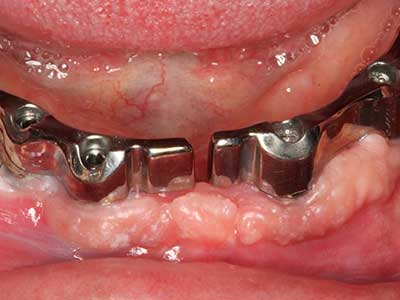

Initial and surgical treatment phases are differentiated in the treatment of marginal periodontitis. In addition to instruction in oral hygiene and motivating patients, both phases should include adequate cleaning of the root surface. In the regenerative setting an open access is generally preferred. The root surface can be cleaned by piezo surgery using special attachments, where instruments with different curvatures are used to reach areas that are difficult to access, such as furcations. The integrated irrigation in the system flushes the detached concrements and bacteria out of the pocket. Specialized systems such as the Piezomed also include application feedback to minimize the ablation of hard dental substance. The greater the pressure on the periodontal attachment the greater the reduction in the amount of ablation.